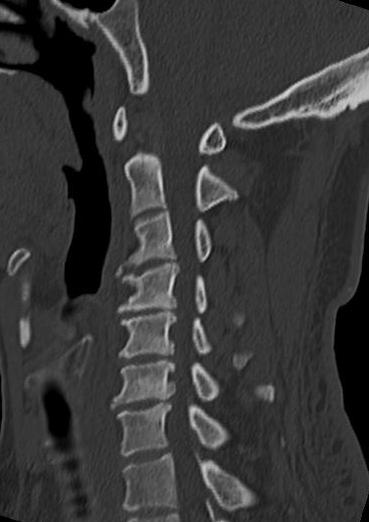

经我院骨病中心脊柱外科医师详细询问病史及查体,并完善相关辅助检查。X线片提示:颈椎生理曲度变直,颈椎骨质增生;CT、MRI提示:颈3/4、颈6/7椎间盘突出,颈4/5椎间盘膨出伴右后突出,右侧椎间孔及椎管狭窄,颈5/6椎间盘膨出伴左后突出,左侧椎间孔及椎管狭窄。综合患者临床症状,最终诊断为混合型颈椎病。

在通过沟通后,骨病中心主任袁毅团队为患者施行显微镜辅助下颈椎前路颈椎间盘切除+椎间植骨融合内固定术(ACDF)。术中在显微镜的辅助下,清楚显露解剖结构,彻底切除椎间盘、骨赘、减压椎间孔,切除后纵韧带,解除脊髓神经压迫,术中出血约20ml。

手术步骤包括减压和重建稳定两大部分。在切除椎间盘组织后,采用显微镜辅助,使手术视野更清晰,手术过程中采用超声骨刀动力系统、磨钻、刮匙等工具切除椎体后方上下缘及钩突后方骨赘,扩大椎间孔,再切除钙化的后纵韧带、充分减压脊髓神经。然后在椎体间植入合适大小的椎间融合器(Cage)恢复椎间隙高度、安装前路钛板,重建椎体间稳定性。